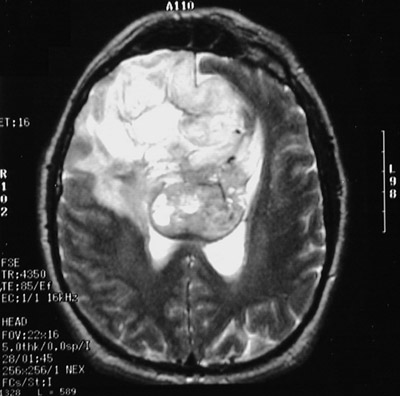

| This T2 weighted fast spin echo MRI scan above in axial view demonstrates a large glioblastoma multiforme involving much of the right cerebral hemisphere. The tumor is variegated and has central necrosis and an irregular border. It crosses the midline via the corpus callosum. The view below is a T2 weighted FLAIR image. |